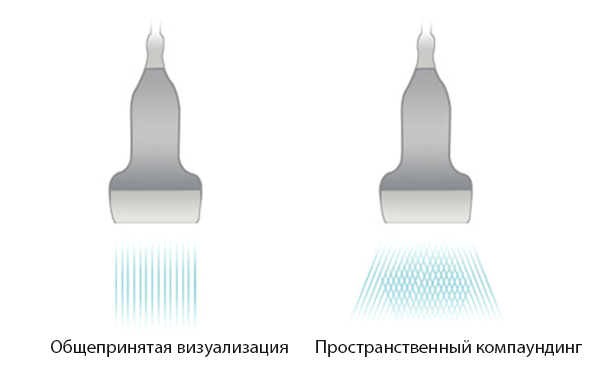

iBeamTM

–ü–æ–∑–≤–æ–ª—è–µ—Ç –∏—Å–ø–æ–ª—å–∑–æ–≤–∞—Ç—å –Ω–µ—Å–∫–æ–ª—å–∫–æ —É–≥–ª–æ–≤ —Å–∫–∞–Ω–∏—Ä–æ–≤–∞–Ω–∏—è –¥–ª—è —Ñ–æ—Ä–º–∏—Ä–æ–≤–∞–Ω–∏—è –µ–¥–∏–Ω–æ–≥–æ –∏–∑–æ–±—Ä–∞–∂–µ–Ω–∏—è, —á—Ç–æ –ø—Ä–∏–≤–æ–¥–∏—Ç –∫ —É–≤–µ–ª–∏—á–µ–Ω–∏—é –∫–æ–Ω—Ç—Ä–∞—Å—Ç–Ω–æ–≥–æ —Ä–∞–∑—Ä–µ—à–µ–Ω–∏—è –∏ —É–ª—É—á—à–µ–Ω–∏—é –≤–∏–∑—É–∞–ª–∏–∑–∞—Ü–∏–∏.